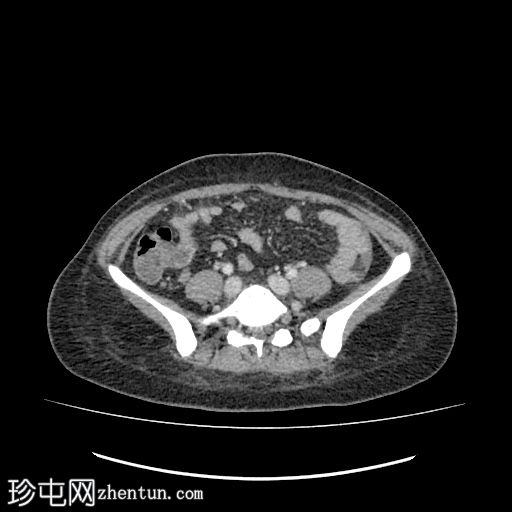

轴位增强扫描

动脉期

肝下区可见一大小约15 x 15.2 x 8.6 cm的较大、边界清晰、呈不均匀强化的实性肿块。

该病灶压迫胃小弯、幽门和胃窦,并对肝脏产生占位效应。门静脉和下腔静脉受压,但脂肪间隙保持完整,未见明确的血管侵犯。

肿块左侧可见正常的胰尾。胰管未见扩张。

腹主动脉旁可见亚厘米级淋巴结,最大者短轴直径为 3.5 mm。

中度弥漫性腹水,少量左侧胸腔积液。